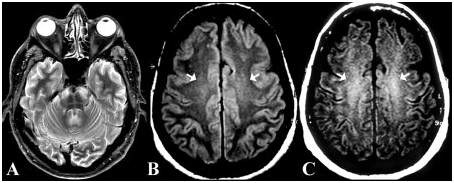

- Магнитно-резонансная томография (МРТ) головного мозга:

- МРТ создает детальные изображения структур головного мозга. Это исследование крайне важно для выявления структурных изменений, таких как опухоли, последствия инсультов, травмы, очаги демиелинизации (при рассеянном склерозе) или признаки нейродегенеративных заболеваний.